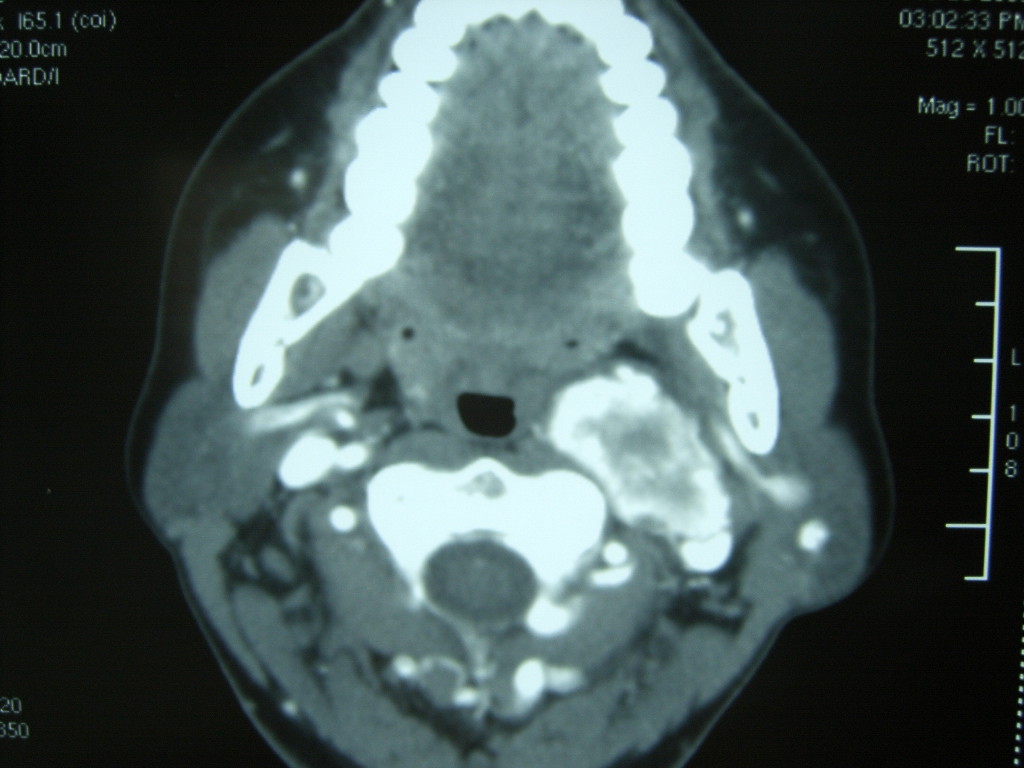

女,48岁,左颈部增粗,不适一年,伴左侧面麻.

增强明显,考虑左侧颈动脉体瘤可能性大。

答案:颈动脉体瘤  此患者已于赤峰220医院手术,